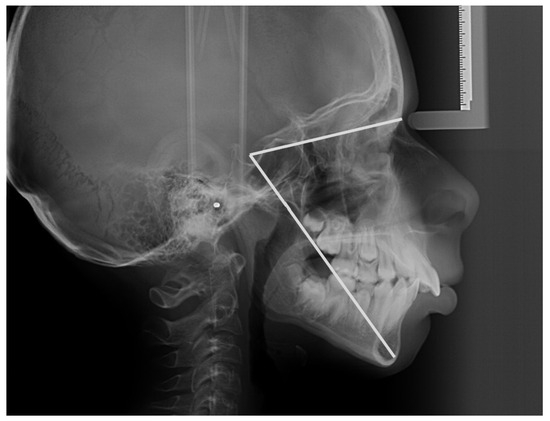

2.1.1. Cephalometric Measurements and Protocol

| 1 | Total Anterior Facial Height | Measured along the N–Me line. |

| 2 | Total Posterior Facial Height | Measured along the S–Go line. |

| 3 | FHR | Jarabak’s ratio, also known as the ratio of TPFH to TAFH multiplied by 100, is calculated. Based on FHR, we classify facial morphology into three patterns: (1) Hyperdivergent growth pattern: FHR < 59%, predominantly vertical growth pattern. (2) Neutral or normodivergent growth pattern: FHR between 59 and 63%. (3) Hypodivergent growth pattern: FHR > 63%, predominantly horizontal growth pattern [18]. According to Ahmed et al., the sum of posterior angles and the Jarabak ratio provide a more accurate measurement of the vertical relationship [19]. |

| 4 | S–Gn (y-axis) Angle | The mandible’s position in relation to the cranial base is defined. A mean value of 66° indicates a posterior mandibular position and a dominance of vertical growth; smaller angles indicate an anterior mandibular position and a dominance of anterior growth [20]. |

- S (sella turcica): located in the middle of the hypophyseal and pituitary fossae.

- N (nasion): the most anterior point of the middle frontonasal suture.

- Go (gonion): the midpoint on the posterior border of each gonial angle, located mediolaterally.

- Me (menton): the lowest point on the chin’s curve [25].